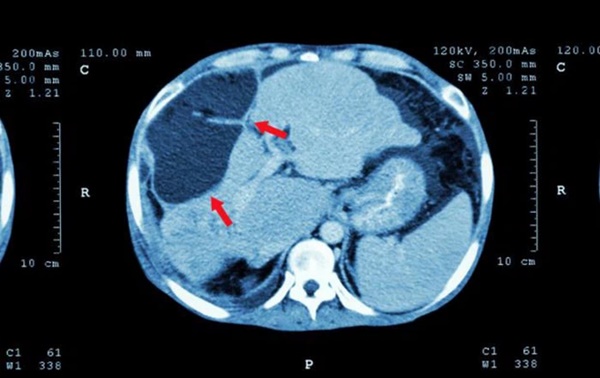

Hình ảnh chụp X-quang cho thấy khối u